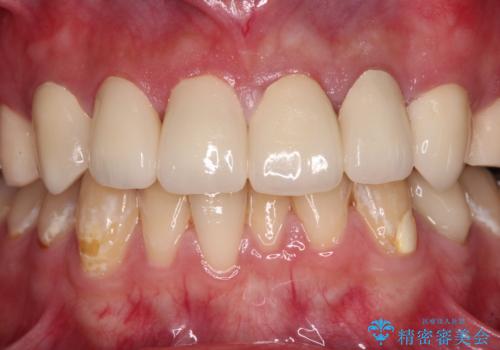

むし歯は多かったものの、歯肉の腫脹はそれほどなかったため、最小限の治療回数で治療を終えることができました。